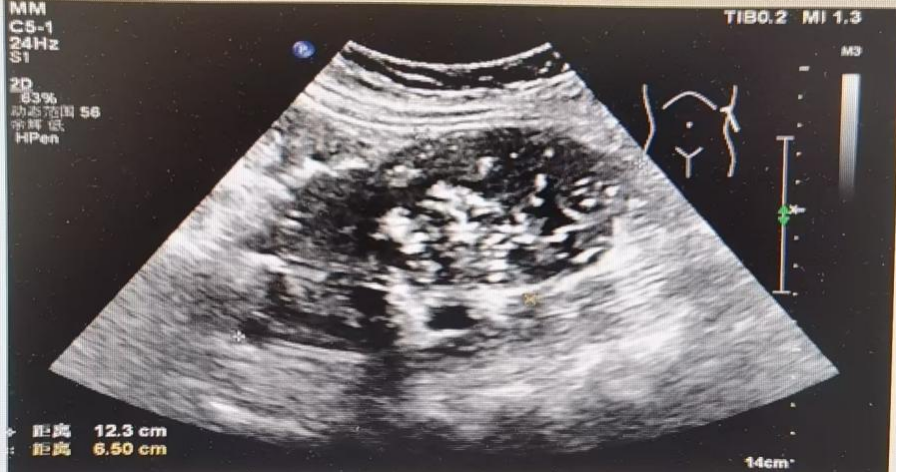

B超(2022.5.17)

▪ 左中上腹实性肿物——考虑恶性,神经母细胞瘤可能性大,大小约12.3×9.9×6.5cm。

▪ 腹膜后多发淋巴结肿大——考虑转移瘤,最大5.1×2.9×2.4cm。

▪ 左颈部多发实性肿物——考虑转移瘤,最大3.8×2.2×1.8cm。